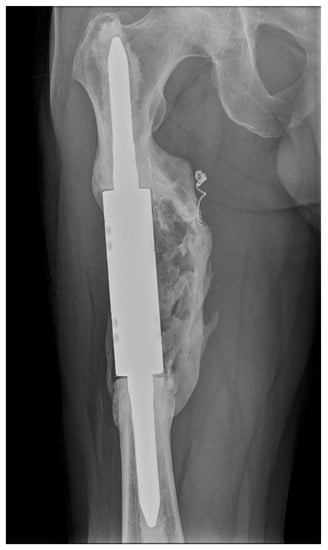

Other factors mentioned in the literature that may affect the failure of intercalary spacers are the resection length, stem lengths, stem anchoring location, type of fixation (cement versus non-cement), stem adjustment and type of prosthesis (individual versus modular). Ruggieri et al. [] mentioned a resection length > 10 cm as the second main risk factor for failure. In our cohort of patients, there was not a significant relationship between the risk of failure and the resection length (the average resection length was 11.3 cm (range 8–16 cm)). According to Fuchs et al. [], there is a contraindication to use intercalary spacers with standard stems to anchor lengths < 5 cm. According to Streitbürger et al. [], the riskiest shaft anchorage is in the metaphyseal and metadiaphyseal locations. Only cemented stems were used in our group of patients. Cemented fixation is associated with increased postoperative function (MSTS score) and fewer complications []. An interesting factor that could minimise the risk of aseptic loosening and thus positively affect implant survival is the formation of heterotopic ossification around the implant, which often forms a bone bridge connecting the proximal and distal bone fragments [,,,]. We have repeatedly observed this condition forming around the reconstructions after resections of kidney cancer metastases (Figure 6).

Figure 6.

X-ray image of an intercalary endoprosthesis with the formation of heterotopic ossification around the implant after the resection of a renal cell carcinoma metastasis, with a bone bridge connecting the proximal and distal bone fragments. This image is from patient 1 in Table 1.